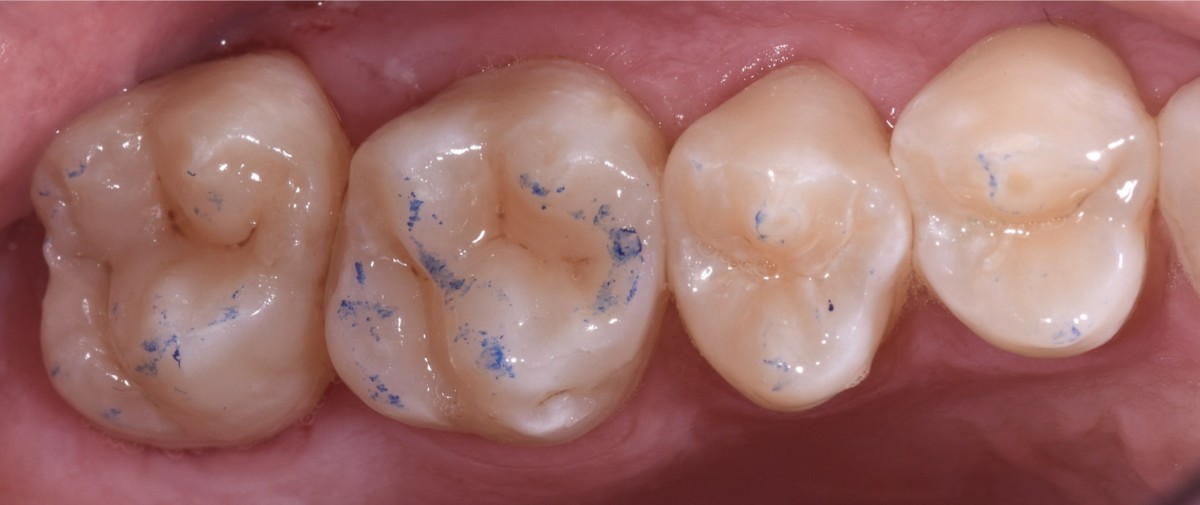

Oral hygiene motivation was carried out, alongside with proper periodontal treatment (scaling, polishing) before taking initial photo and rx bitewing of the quadrant (Fig.1).

Restorations immediately after rubber dam removal with occlusal contacts (Fig.9).